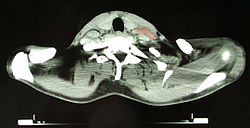

Oberflächlich gelegene Lymphknoten lassen sich mit den Fingern tasten. Für genauere Untersuchungen und die Darstellung tiefer Lymphknoten finden Ultraschall, Computertomografie (CT), Magnetresonanztomografie (MRT), Lymphografie und Szintigrafie Anwendung.

Die anatomische Struktur des Lymphknotens kann im Ultraschall dargestellt werden und zeigt als Normalbefund einen fettigen echoarmen Hilus. Bei unspezifisch reaktiv veränderten Lymphknoten wird dieses Hiluszeichen betont und der Lymphknoten behält seine ovale Form. Ein Fehlen des Hiluszeichens kann auf eine Infiltration durch ein Malignom hinweisen. Sowohl bei reaktiven als auch malignen Lymphknoten kann sich eine Hypervaskularisation zeigen. Ein Verlust der ovalen Form zu Gunsten einer kreisrunden Form des Lymphknotens kann ebenso auf eine Malignominfiltration hinweisen. Nekrosen im Lymphknoten zeigen sich oft echofrei und können sowohl durch abscedierende Infektionen wie auch Einschmelzung einer Tumorabsiedlung entstehen.[7]

Durch eine gezielte Gewebsprobe (Biopsie) aus dem Lymphknoten oder die chirurgische Entnahme eines auffälligen Lymphknotens kann Untersuchungsmaterial für eine histopathologische Untersuchung gewonnen werden.